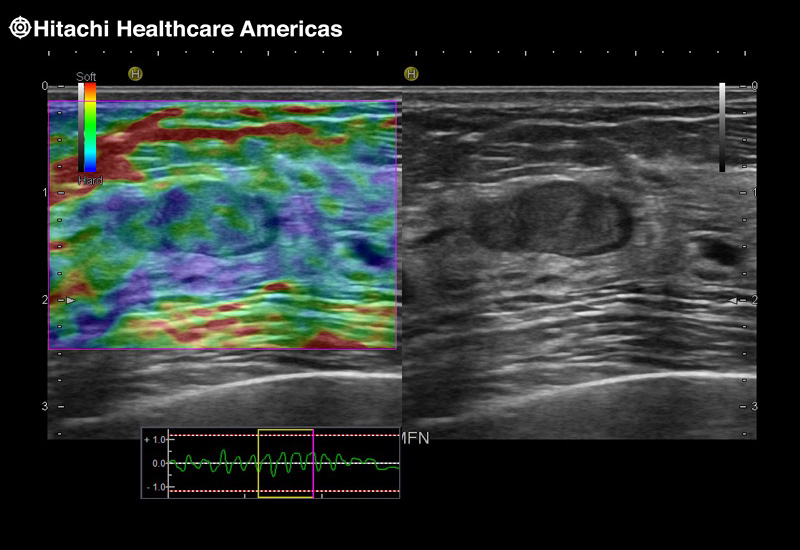

Fujifilm Healthcare's dedication to Surgeons provides outstanding ultrasound technology, professional support and the specialized tools necessary to best perform comprehensive real-time ultrasound imaging in Breast Surgery, General Surgery, Laparoscopic Surgery, Neurosurgery, Robotic Surgery and Surgical Oncology.

Recognized for our outstanding image quality, outstanding system reliability and intuitive use of cutting edge technology, Fujifilm Healthcare remains the standard in the field of Surgery.

Recognized for our outstanding image quality, outstanding system reliability and intuitive use of cutting edge technology, Fujifilm Healthcare remains the standard in the field of Surgery.

A critical function of robotic ultrasound guidance is tumor margin identification. Fujifilm's family of robotic probes all have the optimum location of the attaching mechanism that allows for full wrist articulation of the probe. The result is an increased confidence that the tumor margins have been completely identified.

Imaging Clearly Defined

State-of-the-art digital architecture and advanced imaging features to redefine the capabilities of surgical ultrasound.